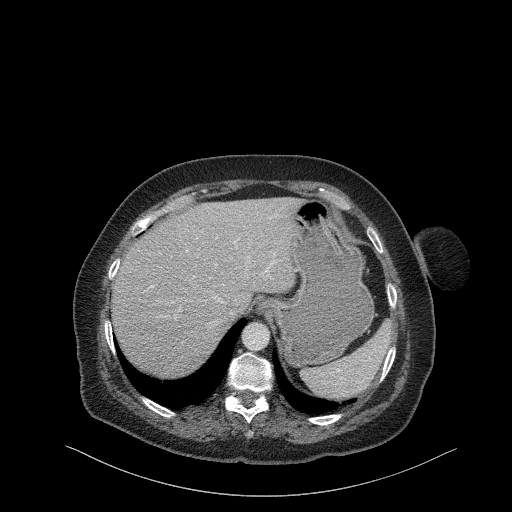

Original NATIVE CT scan (input)

Full window (WL 1023.5, WW 4095 β Low β1024, High +3071)

Actual HU range: [-160.0, 240.0]

Lung window (WL -600, WW 1500 β Low β1350, High +150)

Actual HU range: [-160.0, 150.0]

Mediastinum window (WL 40, WW 400 β Low β160, High +240)